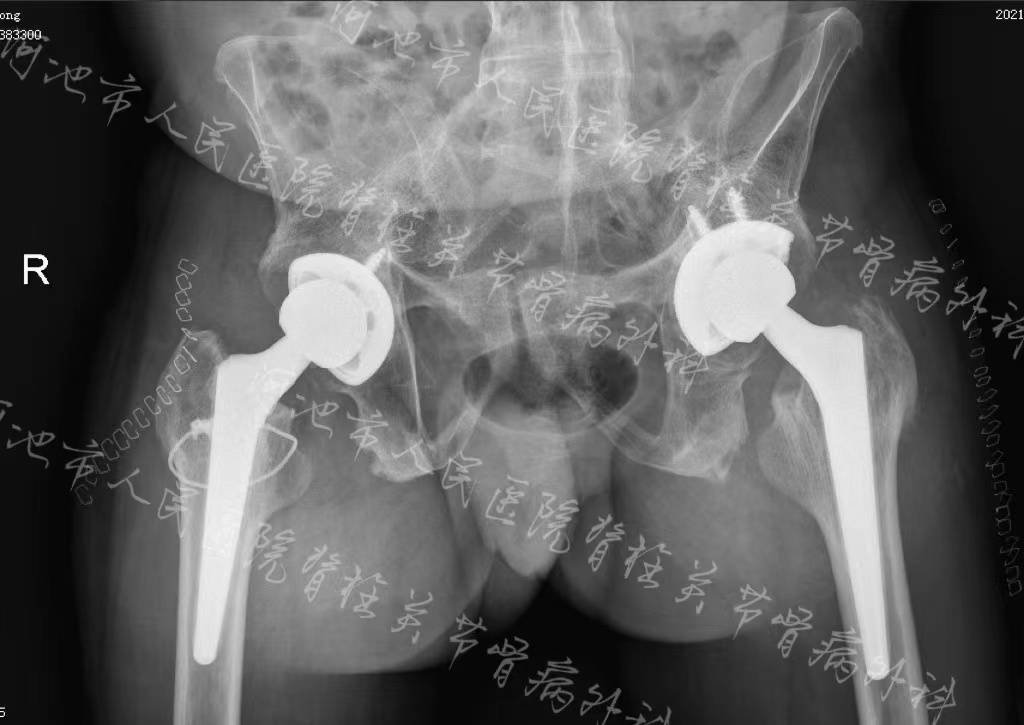

术后影像学检查结果

手术当日,麻醉科采取清醒下全麻插管和术中监护,在脊柱关节骨病外科团队的详细设计、精确操作以及手术室护理组的全力配合下,经过3个小时的手术,成功为患者完成双侧人工髋关节置换,解除了双侧髋关节强直的问题,髋关节功能得到极大改善,并且腰背部的紧张感及双下肢屈曲挛缩也得到了缓解,术后康复治疗师细心指导康复锻炼,让患者生活质量明显改善,为后续脊柱矫形手术打下了很好的基础。